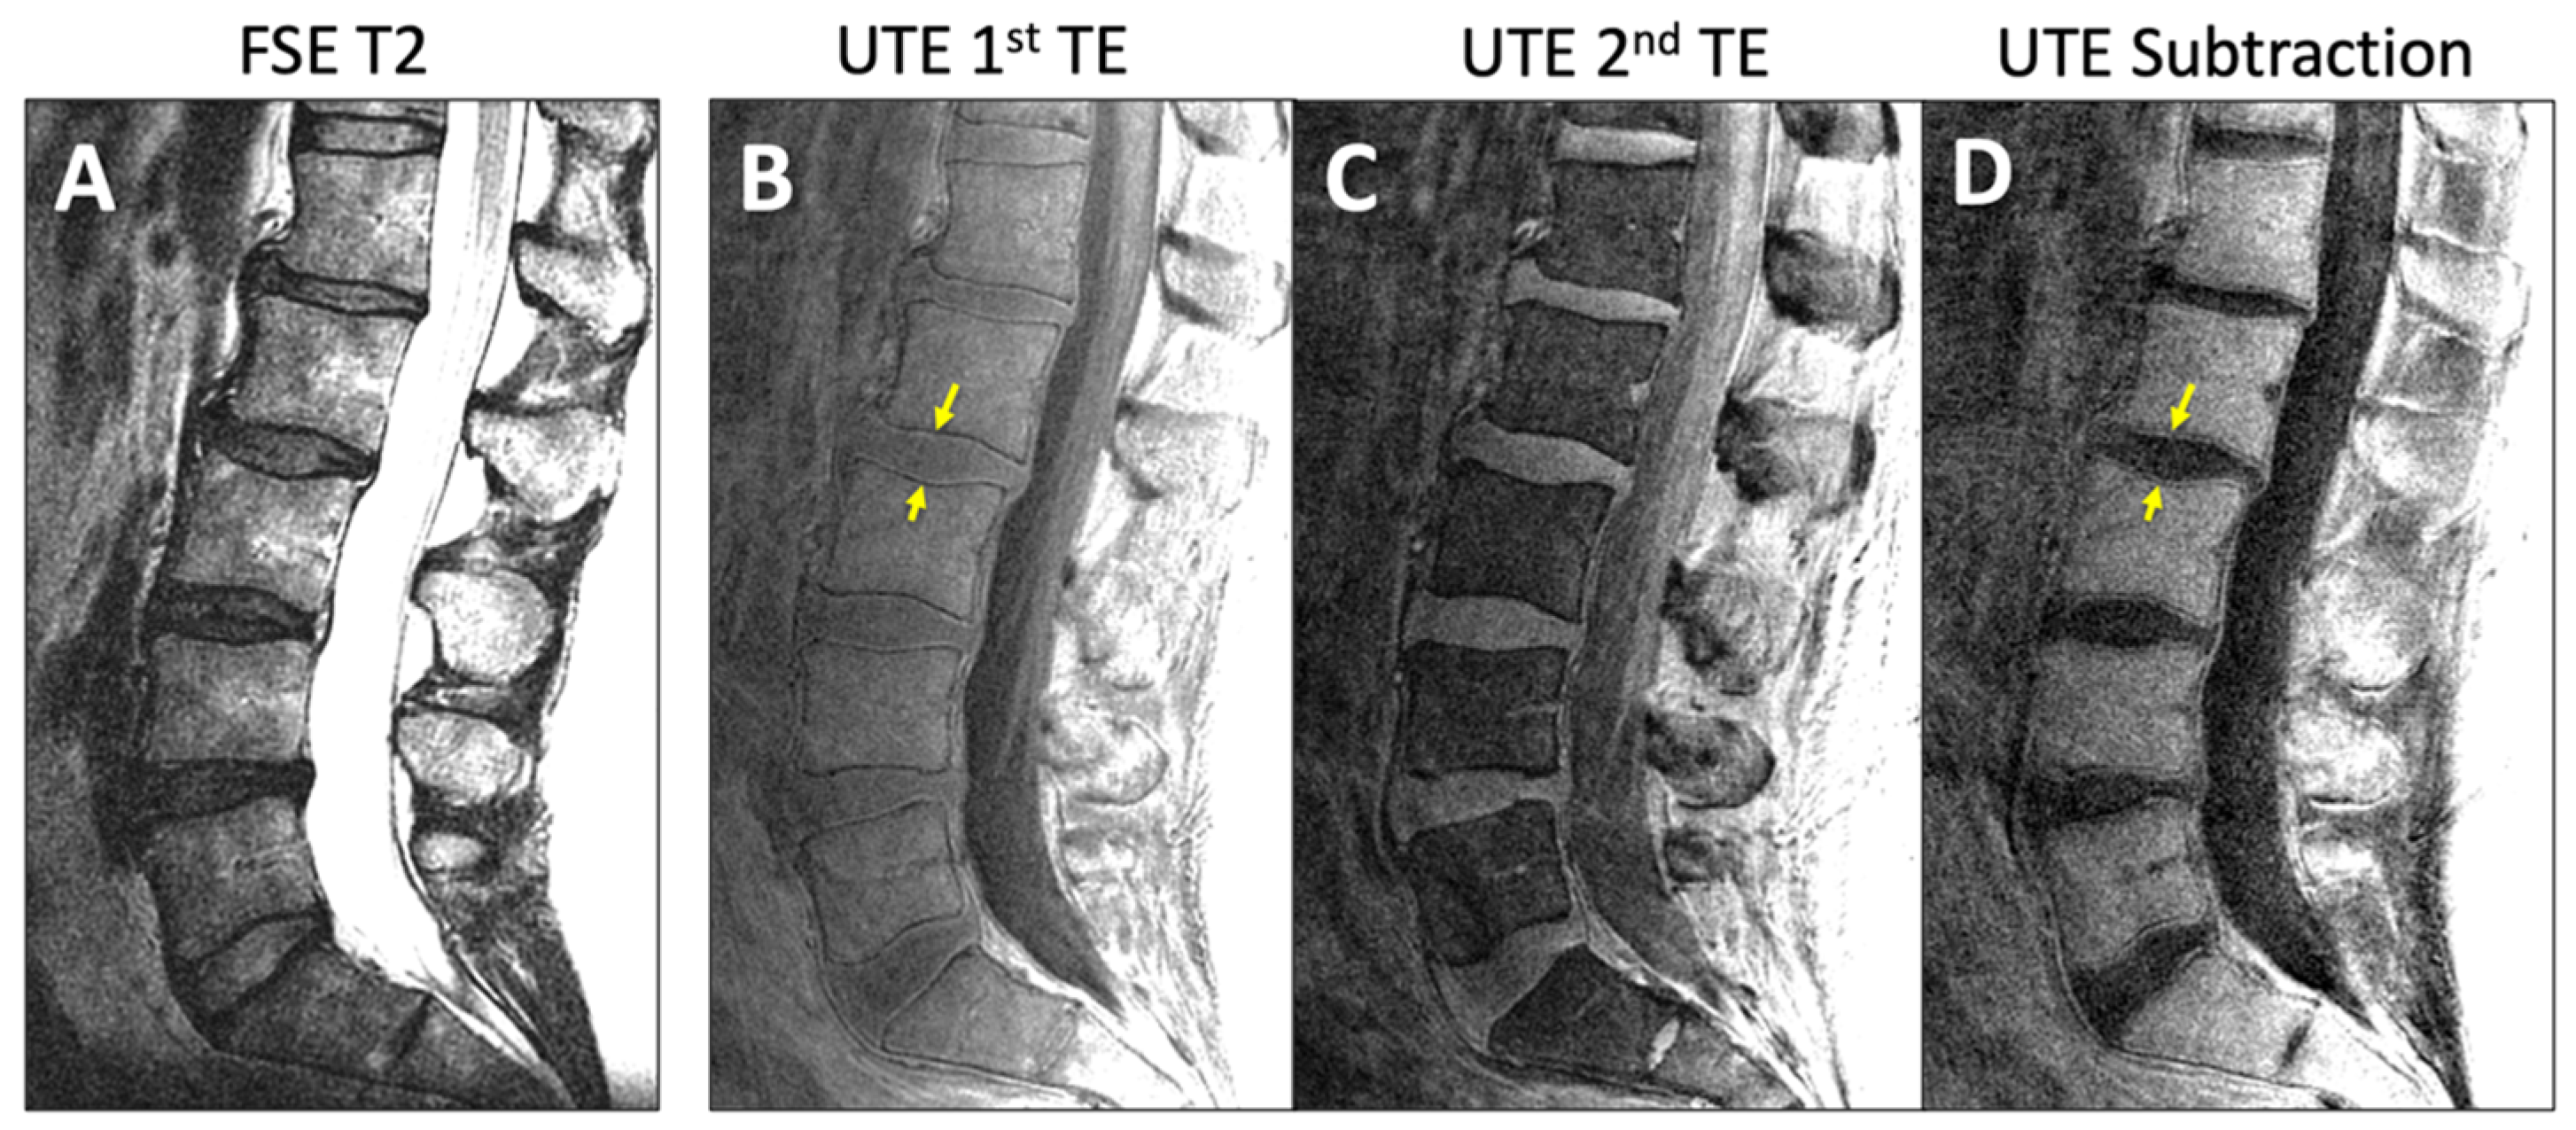

- Finkenstaedt, T.; Siriwananrangsun, P.; Masuda, K.; Bydder, G.M.; Chen, K.C.; Bae, W.C. Ultrashort time-to-echo MR morphology of cartilaginous endplate correlates with disc degeneration in the lumbar spine. Eur. Spine J. 2023, 32, 2358–2367. [Google Scholar] [CrossRef]

- Robson, M.D.; Gatehouse, P.D.; Bydder, M.; Bydder, G.M. Magnetic resonance: An introduction to ultrashort TE (UTE) imaging. J. Comput. Assist. Tomogr. 2003, 27, 825–846. [Google Scholar] [CrossRef]

- Chen, K.C.; Tran, B.; Biswas, R.; Statum, S.; Masuda, K.; Chung, C.B.; Bae, W.C. Evaluation of the disco-vertebral junction using ultrashort time-to-echo magnetic resonance imaging: Inter-reader agreement and association with vertebral endplate lesions. Skelet. Radiol. 2016, 45, 1249–1256. [Google Scholar] [CrossRef] [PubMed]

- Law, T.; Anthony, M.P.; Chan, Q.; Samartzis, D.; Kim, M.; Cheung, K.M.; Khong, P.L. Ultrashort time-to-echo MRI of the cartilaginous endplate: Technique and association with intervertebral disc degeneration. J. Med. Imaging Radiat. Oncol. 2013, 57, 427–434. [Google Scholar] [CrossRef] [PubMed]

- Ji, Z.; Li, Y.; Dou, W.; Zhu, Y.; Shi, Y.; Zou, Y. Ultra-short echo time MR imaging in assessing cartilage endplate damage and relationship between its lesion and disc degeneration for chronic low back pain patients. BMC Med. Imaging 2023, 23, 60. [Google Scholar] [CrossRef]